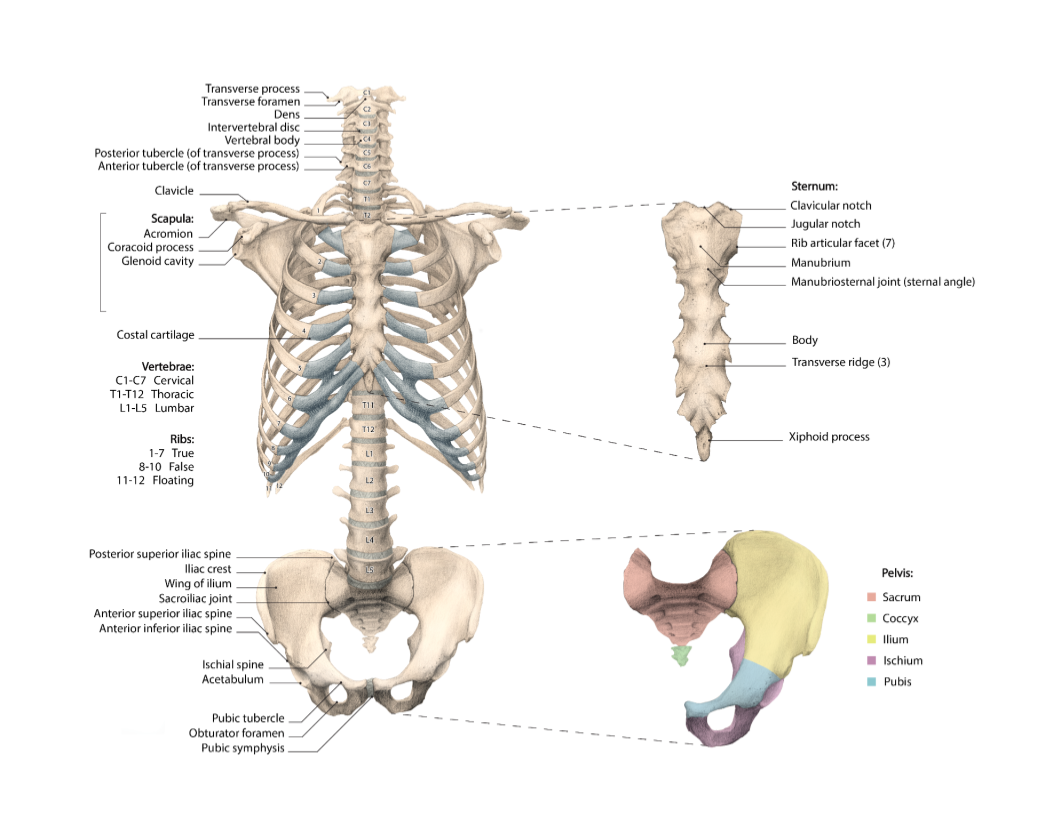

“Torso - Thoracic Cage, Vertebral Column, and Pelvis”

Final textbook figure

Overview:

Explored by means of observation, measuring, and drawing the structural interdependency of the human thorax, abdomen and pelvis. Drew a ventral view of the skeleton of a human torso (vertebral column, thorax and pelvis), the scapula, and clavicula, as detailed as possible at 1:1 scale. Added the appropriate nomenclature.

Form and negative space, proportions, simple foreshortening perspective, precise drawing technique

Final Product:

Medical textbook figure for medical students - graphite